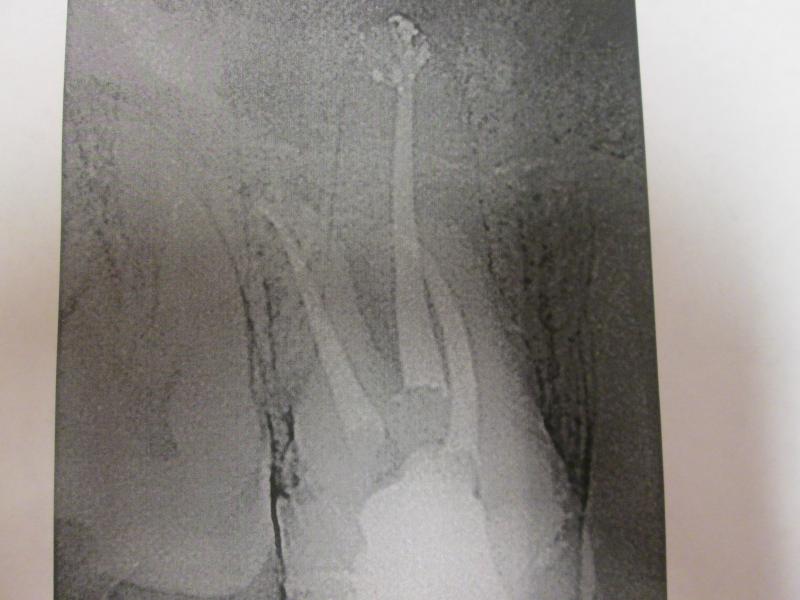

DR JET LOVES ROOT CANALS

General Dentist,  Performs Root Canals ONLY - Microscope Trained Dentist

"DR. JET'S MISSION IS TO PERFORM  ROOT CANALS FOR A REDUCED FEE USING THE LATEST TECHNOLOGY  AND TECHNIQUES TO SERVICE THE MANY PEOPLE WHO ARE UNINSURED OR UNDER-INSURED GIVING EVERYONE AN OPPORTUNITY TO SAVE THEIR TOOTH!"

ROOT CANALS by DR. JET (Jetepon Chiranand DDS)